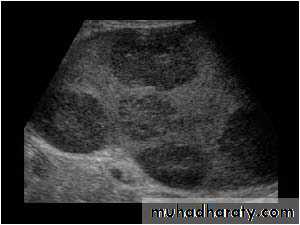

Benign lesions

Hemangioma